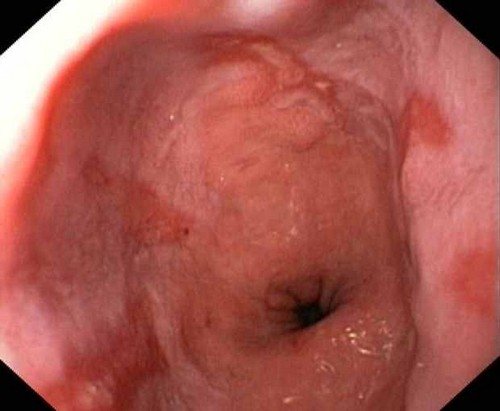

Как выглядит

В результате развития рефлюкс эзофагита можно увидеть изменения контуров пищевода, изъязвления, отечность стенок и скопление слизи.

Эндоскопическое исследование является определяющим для постановки диагноза ГЭРБ. В ходе исследования есть возможность оценить состояние слизистой оболочки пищевода, а также степень выраженности моторных нарушений в области пищеводно-желудочного перехода. Для наиболее объективной оценки мы предлагаем пользоваться эндоскопическими критериями G. Tytgat (1990) в модификации (табл. 2).

Пример эндоскопического заключения: «Рефлюкс-эзофагит II-В степени».